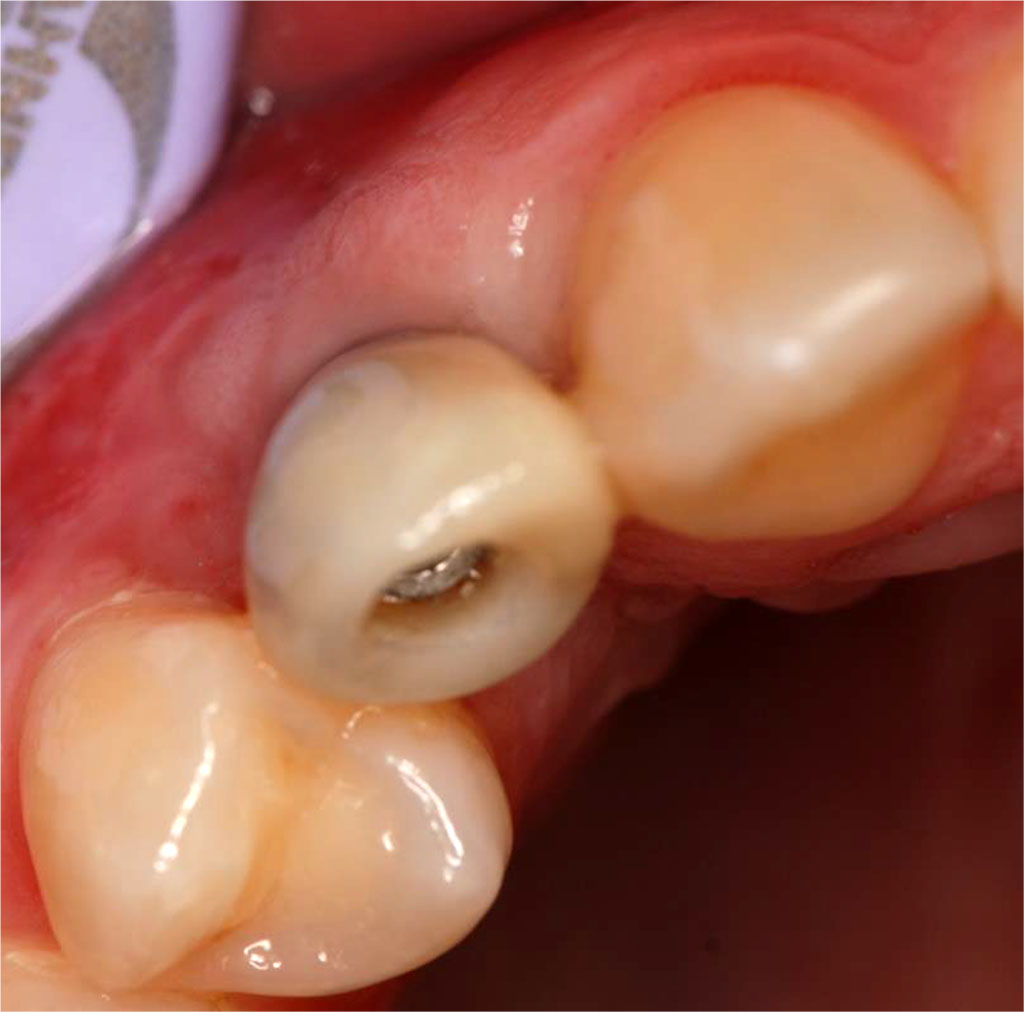

After 7 days, the sutures were removed from the donor site region. The patient reported complaints of pain in the area of the donor site (in the area of the recipient site, these were almost imperceptible). A non-violent swelling was observed on the right side of the anterior maxilla. After two weeks, the sutures from the recipient site were removed and normal healing of the palate and recipient site was observed (patient continued to complain of donor site tenderness) (Fig.13). The condition of the soft tissues after a period of 3 months was aesthetically satisfactory, both for the operator and the patient, and the thickness of the keratinised gingiva over the implant in position 13 measured was 1.5 mm (Tab. 1). The width of the keratinised gingiva in the indicated area increased by 2.5 mm (Tab.1). A procedure was performed to expose the implant with augmentation of the surrounding soft tissues using the roll-flap technique, and after a period of one week, a temporary crown was placed (Fig.14).

Fig.13 Tissue condition one month after the surgical procedure.

Fig.14 Tissue condition after augmentation procedures with a temporary crown in place (occlusal view).